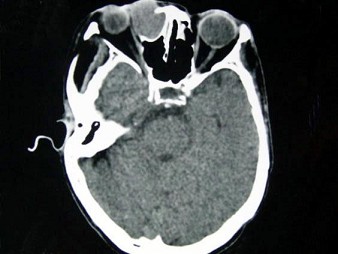

女,40岁,右眼反复溢泪伴眼球渐进性突出2年余,眼球运动受限,CT检查如图所示,最可能的诊断是()

女,40岁,右眼反复溢泪伴眼球渐进性突出2年余,眼球运动受限,CT检查如图所示,最可能的诊断是()<img border="0" style="width: 338

[单选题]女,40岁,右眼反复溢泪伴眼球渐进性突出2年余,眼球运动受限,CT检查如图所示,最可能的诊断是()A.泪腺囊肿B.泪囊囊肿C.泪腺血肿D.泪囊血肿E.

女性,40岁,右眼反复溢泪伴眼球渐进性突出2年余,眼球运动受限,CT检查如图所示,请选择最可能()<img border="0" style="width: 187

[单选题]女性,40岁,右眼反复溢泪伴眼球渐进性突出2年余,眼球运动受限,CT检查如图所示,请选择最可能()A.泪腺囊肿B.泪囊囊肿C.泪腺血肿D.泪囊血肿E.

女,40岁,右眼反复溢泪伴眼球渐进性突出2年余,眼球运动受限,CT检查如图所示,

[单选题]女,40岁,右眼反复溢泪伴眼球渐进性突出2年余,眼球运动受限,CT检查如图所示,最可能的诊断是()A . 泪腺囊肿B . 泪囊囊肿C . 泪腺血肿D . 泪囊血肿E . 眶内结核

女性,40岁,右眼反复溢泪伴眼球渐进性突出2年余,眼球运动受限,CT检查如图所示

[单选题]女性,40岁,右眼反复溢泪伴眼球渐进性突出2年余,眼球运动受限,CT检查如图所示,请选择最可能()A .泪腺囊肿B .泪囊囊肿C .泪腺血肿D .泪囊血肿E .眶内结核